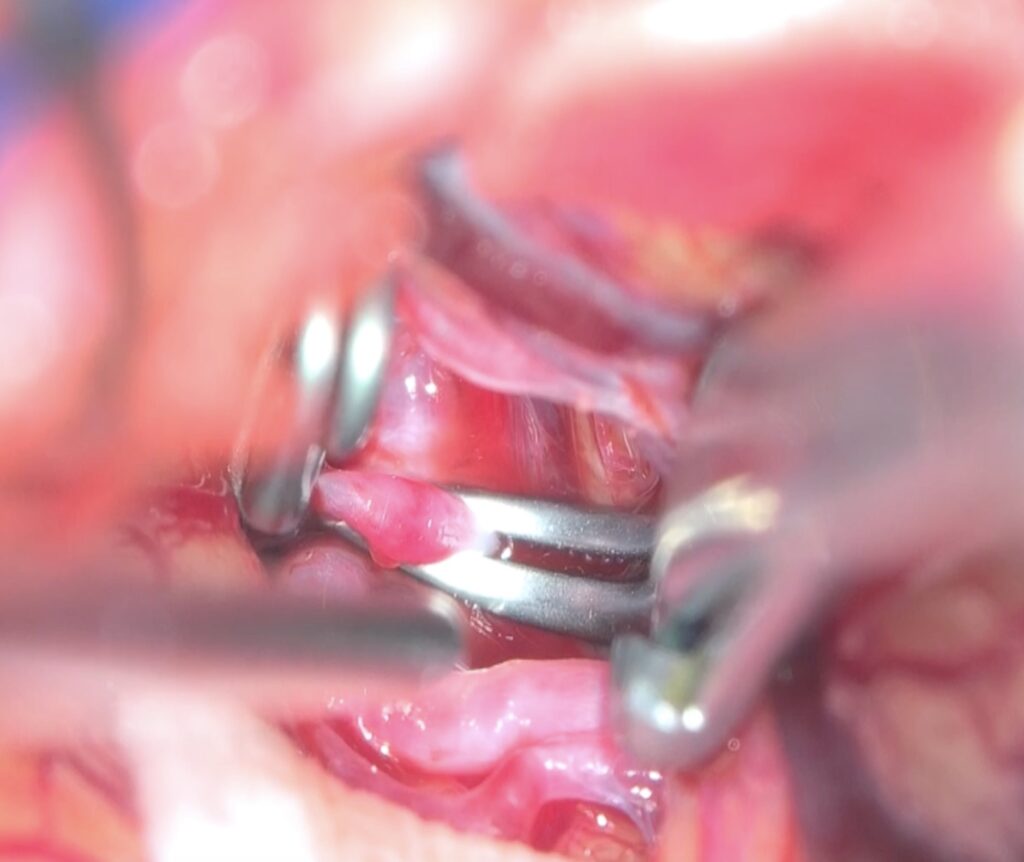

2604月、59歳女性の左海綿静脈洞内髄膜腫(複視)に対して左内頸動脈のための左STA-MCAバイパスを行いました。

260331 60歳男性 頭蓋咽頭腫を開頭で摘出しました。